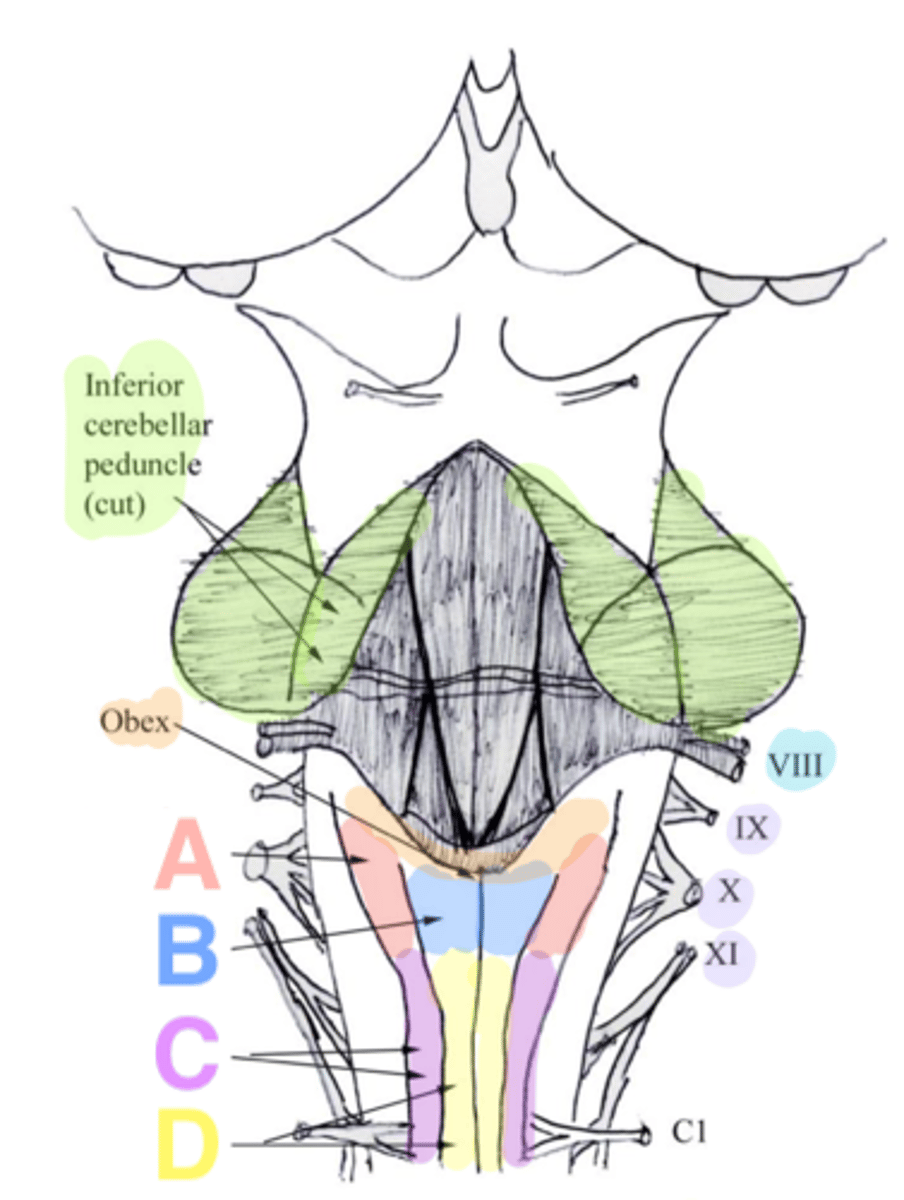

white matter stalks that connect the medulla to the cerebellum

**these help to form the lateral walls of the caudal portion of the 4th ventricle

inferior cerebellar peduncles

V-shaped boundary of the caudal aspect of the 4th ventricle that marks the boundary between the open and closed portions of the medulla

obex

Which cranial nerves arise from the medulla? (and pontomedullary junction)

6-10, 12

inferior cerebellar peduncles

cuneate tubercle

gracilis tubercle

cuneatus tract

gracilis tract

obex